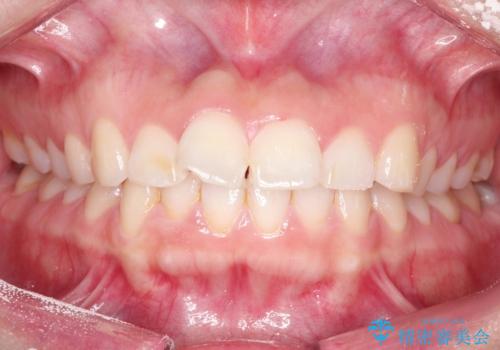

【インビザライン】前歯が出ているのを治したい

- 前歯が出ていることを主訴に来院されました。

前歯の突出感が改善され、満足していただきました。